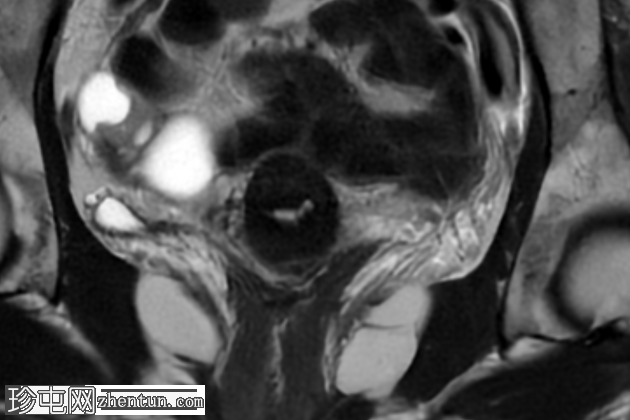

轴位T1加权像

增强脂肪抑制像

盆腔MRI显示右侧卵巢解剖位置可见一边界清晰的卵圆形肿块。该病灶由囊性和实性成分组成。囊性部分壁薄,在T2加权像上呈均匀高信号,在T1加权脂肪抑制序列上呈低信号,无对比剂增强。该实性成分的信号特征与正常卵巢组织相似,DWI成像未见扩散受限,静脉注射造影剂后未见异常强化。

此外,在子宫左侧壁可见一管状薄壁囊性结构,延伸至同侧髂外血管,末端呈盲端。该结构在T2加权像上呈均匀高信号,在T1加权脂肪抑制序列上呈低信号,且无造影剂强化。

本例中,盆腔MRI显示,患者右侧卵巢解剖位置存在一个边界清晰的附件肿块,该患者有20年前行双侧输卵管卵巢切除术的病史。该病灶包含囊性和实性成分,其中实性部分表现出与正常卵巢组织相似的信号特征。无扩散受限和无可疑的增强扫描强化提示排除恶性病变。这些影像学特征结合相关的手术史进行解读,符合残留卵巢组织的特征,支持卵巢残留综合征的诊断。此外,还发现对侧子宫左侧延伸出一个管状薄壁囊性结构,末端呈盲端。其形态、信号特征和无强化表现符合输卵管残端或输卵管残端积水,这是输卵管切除术后常见的术后表现。附件残余的存在进一步支持术后病因,而非原发性妇科肿瘤

主要鉴别诊断包括腹膜包涵囊肿、子宫内膜异位症相关囊肿和附件肿瘤。腹膜包涵囊肿通常位于腹膜腔内,不含类似卵巢组织的实性成分。子宫内膜异位囊肿通常在T1加权像上表现为高信号,T2加权像上出现阴影,并具有其他特征性MRI表现,而本例4中均未见这些表现。鉴于无扩散受限、无可疑强化以及实性成分的良性影像学表现,肿瘤性病变的可能性较小。